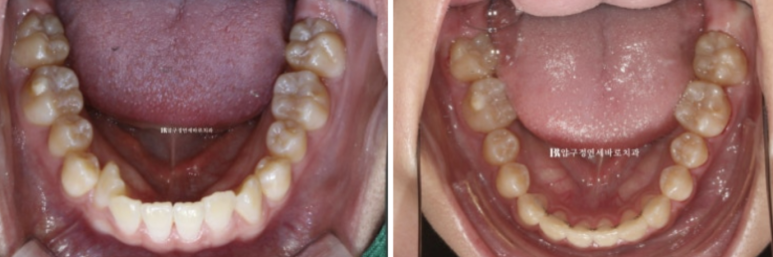

23.07

내려와 있는 송곳니쪽에 미니스크류를 심어 교합평면을 맞추고

앞니에 파란색 레진 부분 바이트 블럭을 올려서 과개교합 개선과 소구치 정출을 도모했습니다.

23.11

전체치료기간은 1년 1개월입니다.

환자분 나이가 어린 편이라 빠르게 마무리가 잘 되었습니다.